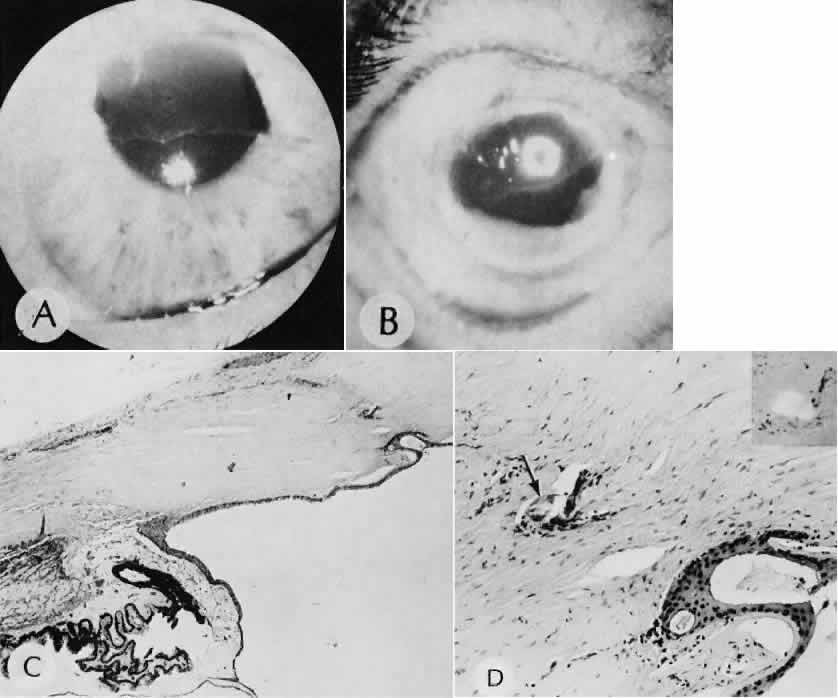

Descemet's membrane is only loosely adherent to the posterior stroma and may be stripped into the anterior chamber at the time of the corneal incision placement (Fig. 27) or injection of sodium hyaluronate. Splitting off of Descemet's membrane from the posterior cornea can lead to postoperative intractable corneal edema.89,90

Fig. 27. A case of stripping of Desce-met's membrane during a filteringprocedure (scleral cautery and iridectomy). A. The clinical appearance was one of extensive filtering bleb formation superiorly and regional dense corneal edema and opacification. B. The anterior chamber remains formed. Detached Descemet's membrane can be seen protruding into the anterior chamber. The patient died shortly after surgery from unrelated causes.C. The gross appearance of the area of detached Descemet's membrane extending into the anterior chamber.D. On the histologic section, the origin of detached Descemet's membraneextends to the region of the limbal wound. (Hematoxylin-eosin stain; × 16.) (Kozart DM, Eagle RC Jr: Stripping of Descemet's membrane after glaucoma surgery. Ophthalmic Surg 12:420–423, 1981.)